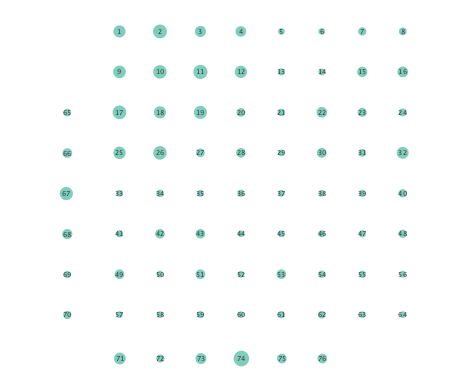

Clustering coefficients are generally used to quantify network cohesion, the tendency for nodes to form groups or communities. Comparison of such coefficients between the preictal and ictal phases may reveal differences in cohesive behavior after onset of a seizure. In the present paper, a per-node clustering coefficient is adopted, and it computes the fraction of triangles in which a node participates out of all possible triangles to which it could possibly belong [24]. Note that a triangle is defined as a fully connected three-node subgraph. Figure 5 depicts clustering coefficients per electrode obtained during the ictal and preictal phases of the ECoG time series. While both the linear and nonlinear models yield changes in the computed coefficients, most nodes have lower clustering coefficients upon seizure onset in the networks inferred via the K-SVARM.

Finally, Figure 6 depicts the closeness centrality computed per node in the inferred networks. Closeness centrality measures how reachable a node is from all other nodes, and is generally defined as the reciprocal of the sum of geodesic distances of the node from all other nodes in the network; see also [24]. Once again, Figure 6 depicts a more general decrease in closeness centralities after seizure onset in networks inferred by the nonlinear SVARM, as compared to the linear variant. This empirical result indicates a change in reachability between regions of the brain during an epileptic seizure.

Moreover, the performance of K-SVARM with data-driven kernel selection was also tested. Figure 7 illustrates the per node degree as well as the closeness centrality of networks inferred from preictal and ictal phases. Consistent with Figures 3 and 6, Figure 7 again reveals universal decrease in node degrees as well as closeness centrality at seizure onset.